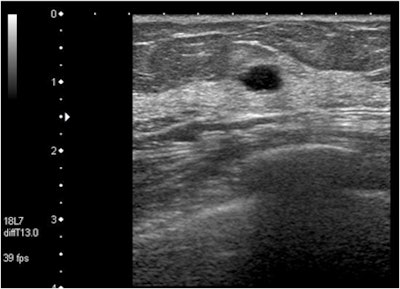

| In this case of invasive ductal carcinoma, CAD increased the mean confidence level from 0.503 without CAD to 0.739. |